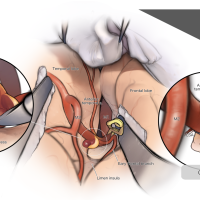

術後イラストシリーズ

脳神経外科(医学書院)寄稿シリーズ

脳神経外科(医学書院) 寄稿シリーズ